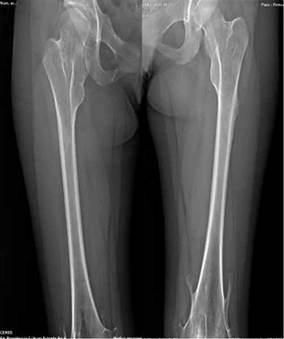

Figura 3:

(C) Proyección AP de fémur izquierdo muestra una exostosis sésil en borde lateral de extremo proximal y dos exostosis pediculadas que surgen de la región metadiafisiaria distal.

(D) Proyección AP de fémur derecho muestra espacio articular coxofemoral incrementado en altura en relación con una subluxación articular, ángulo cérvico diafisario de 150 grados (coxa valga), exostosis pediculada en epífisis distal.